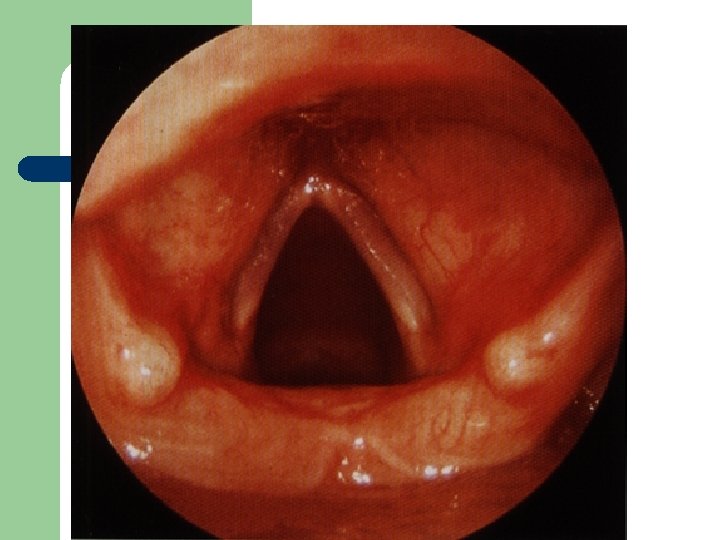

Vývoj dětské chraptivosti l 1. 2. 3. 4. Průvodním jevem při dětské chraptivosti je pokašlávání a pochrchlávání. Nález na hlasivkách postupuje takto: Hyperemické (překrvené hlasivky, Hypertrofické, vřetenovité zduření, hlasivkový uzávěr je neúplný a hlas má dyšnou příměs, ventrikulární řasy se začínají vyklenovat Zpěvácké uzlíčky, nejčastěji na hranicích přední a střední třetiny hlasivek Atrofie hlasivek až s podélnou rýhou, při fonaci nedomykavost uzávěru.

Hlasivkové uzlíky l